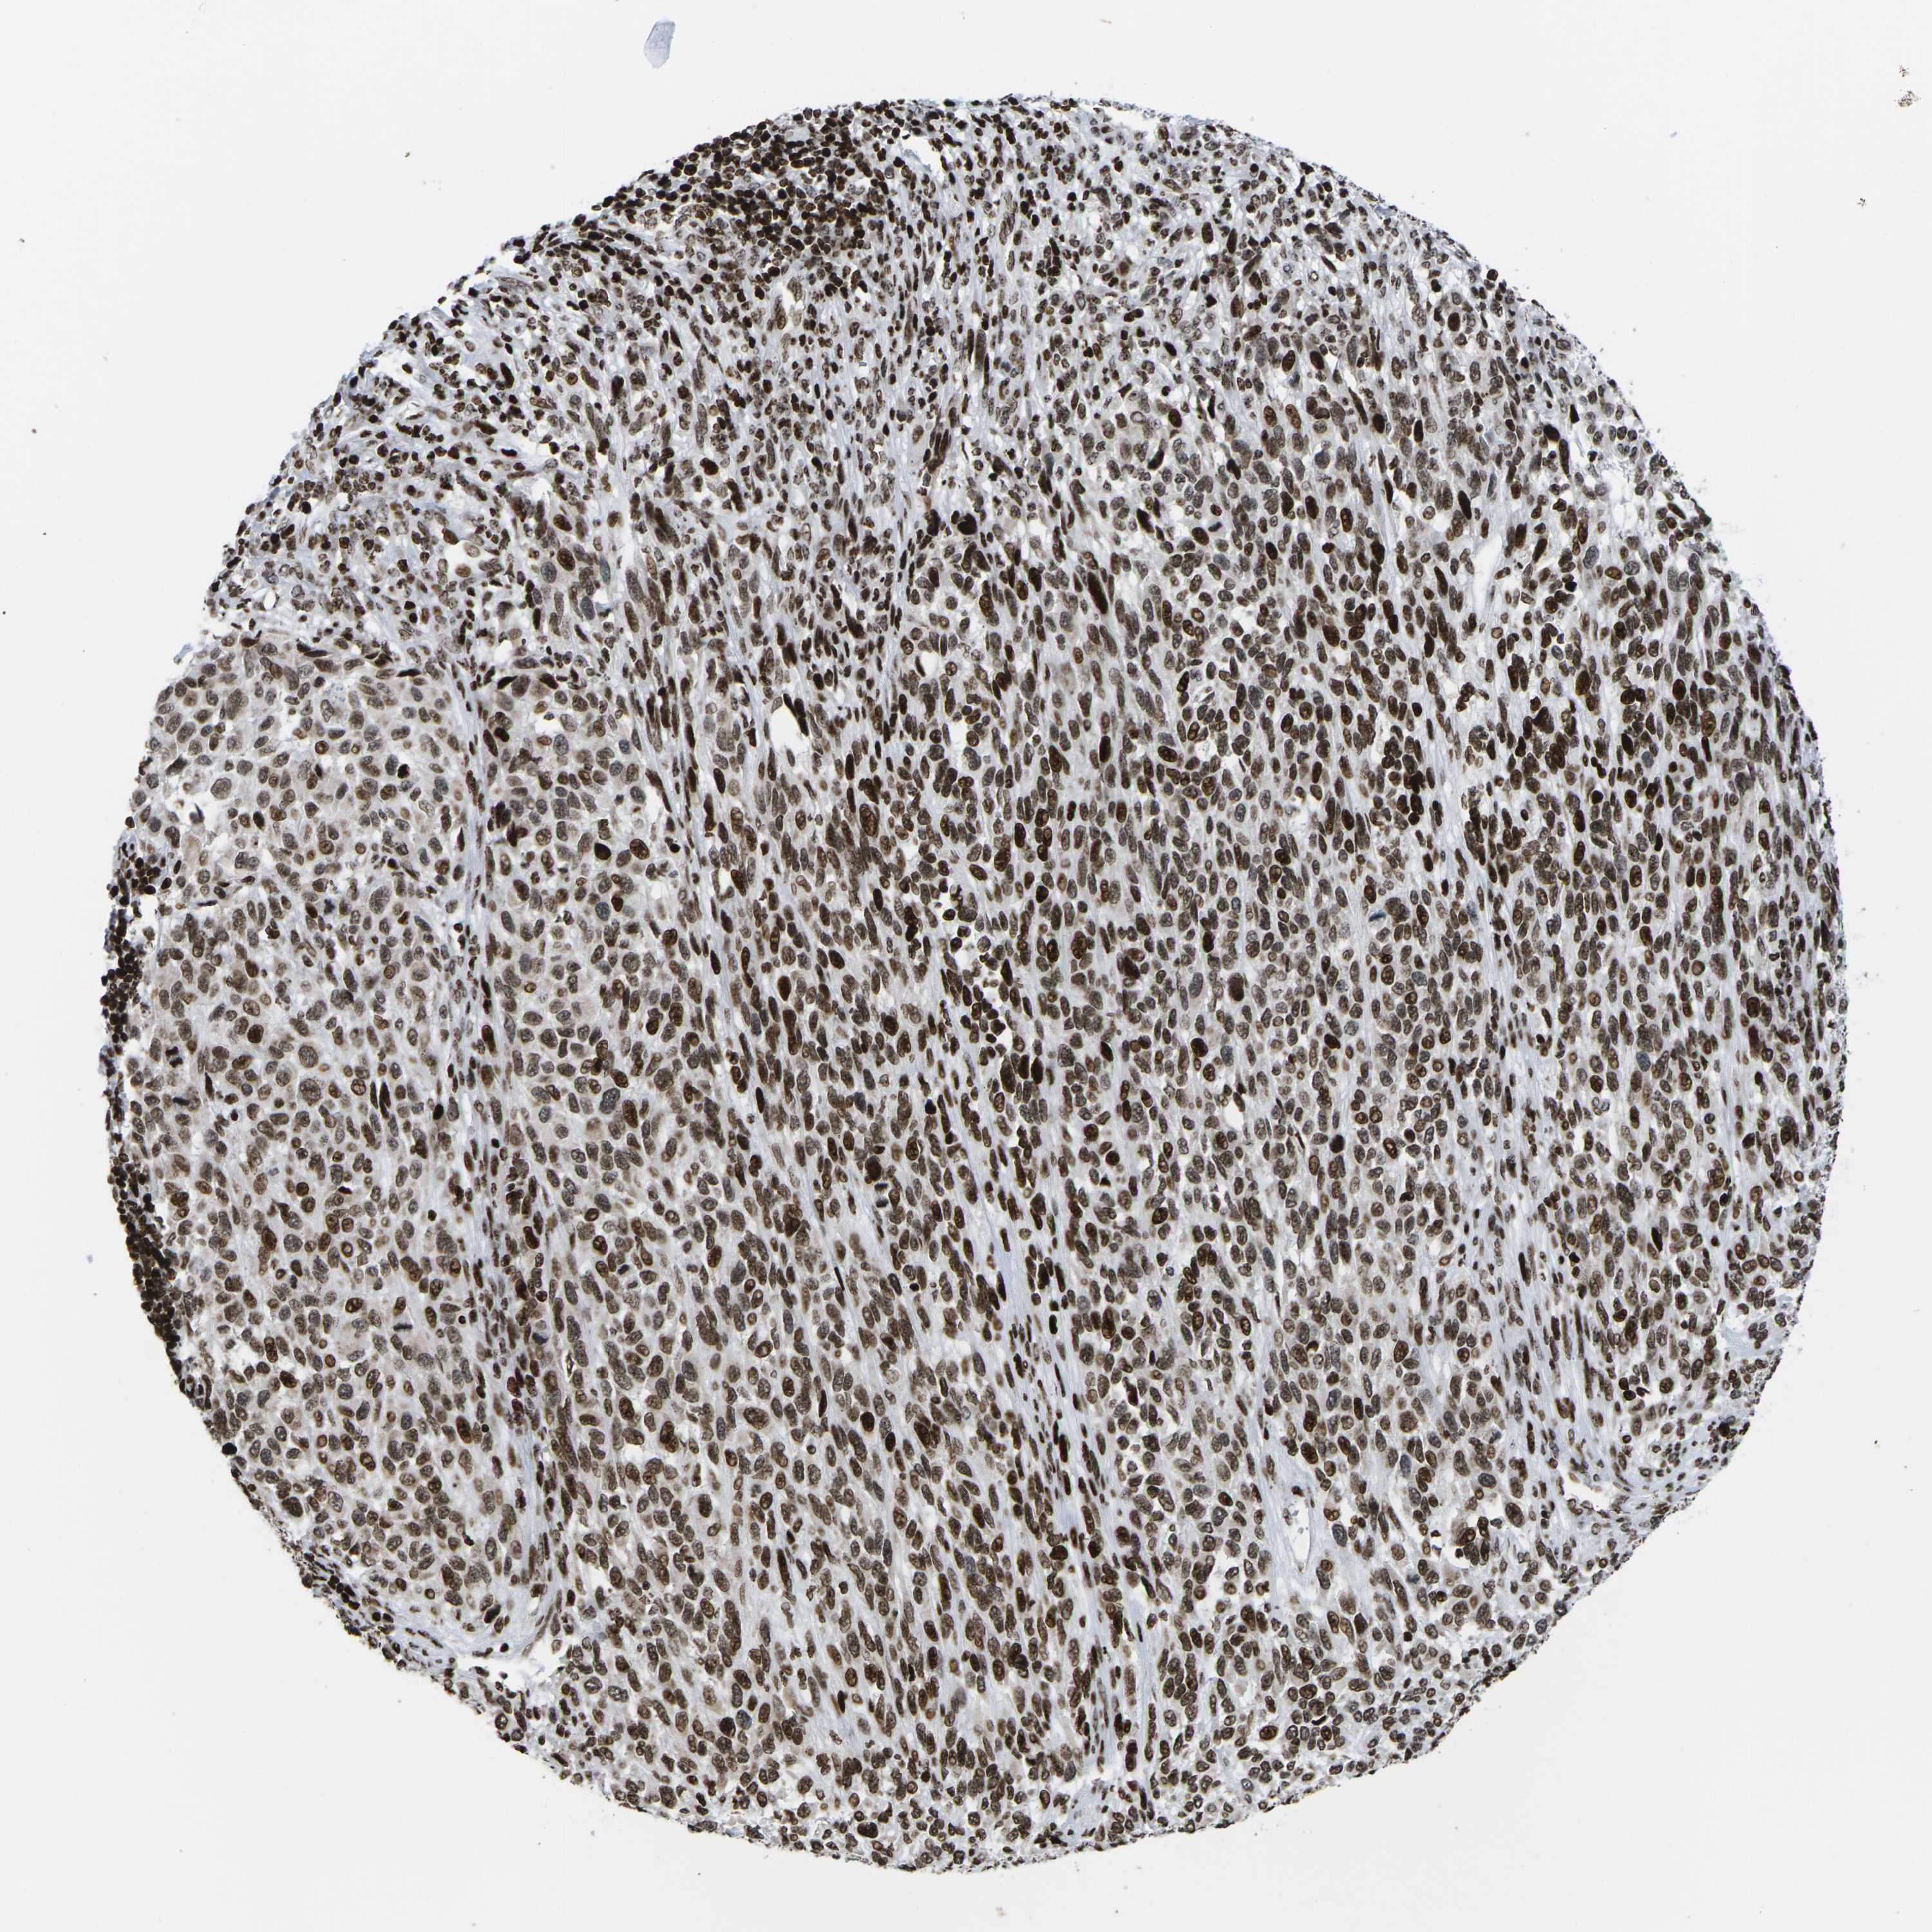

MELANOMA - Protein expressioni

A mouse-over function shows sample information and annotation data. Click on an image to view it in a full screen mode. Samples can be filtered based on level of antibody staining by selecting one or several of the following categories: high, medium, low and not detected. The assay and annotation is described here.

Note that samples used for immunohistochemistry by the Human Protein Atlas do not correspond to samples in the TCGA dataset.

Antibody stainingi

Antibody staining in the annotated cell types in the current human tissue is reported as not detected, low, medium, or high, based on conventional immunohistochemistry profiling in selected tissues. This score is based on the combination of the staining intensity and fraction of stained cells.

Each image is clickable and will lead to virtual microscopy that enables deeper exploration of all samples and also displays staining intensity scores, fraction scores and subcellular localization as well as patient and tissue information for each sample.

Antibody HPA055907

Antibody CAB011506

Staining

High

Medium

Low

Not detected

Intensity

Strong

Moderate

Weak

Negative

Quantity

>75%

75%-25%

<25%

None

Location

Nuclear

Cytoplasmic/membranous

Cytoplasmic/membranous,nuclear

Malignant melanoma, NOS

Malignant melanoma, Metastatic site